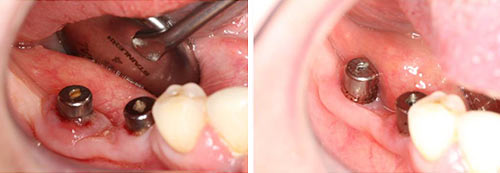

Peri-implant Mucositis

Courtesy of: Bogdan Crisan, DMD, PhD

Laser source: TwinLight®: Nd:YAG (1064 nm) + Er:YAG (2940 nm)

Peri-implantitis

Courtesy of: Aslan Gokbuget, DDS, PhD